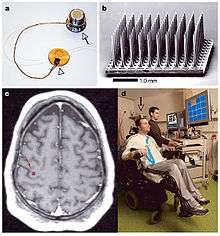

History of electrodes in the brain: In 1878 Richard Canton discovered that electrical signals transmitted through an animal's brain. In 1950 Dr. Jose Delgado invented the first electrode that was implanted in an animal's brain, using it to make it run and change direction. In 1972 the cochlear implant, a neurological prosthetic that allowed deaf people to hear was marketed for commercial use. In 1998 researcher Philip Kennedy implanted the first Brain Computer Interface (BCI) into a human subject.[1]

Using stereotaxy neurosurgeons can approach a minute target in the brain through a minimal opening. This is used in functional neurosurgery where electrodes are implanted or gene therapy is instituted with high level of accuracy as in the case of Parkinson's disease or Alzheimer's disease. Using the combination method of open and stereotactic surgery, intraventricular hemorrhages can potentially be evacuated successfully.[10] Conventional surgery using image guidance technologies is also becoming common and is referred to as surgical navigation, computer assisted surgery, navigated surgery, stereotactic navigation. Similar to a car or mobile Global Positioning System (GPS), image guided surgery systems, like Curve Image Guided Surgery and StealthStation, use cameras or electromagnetic fields to capture and relay the patient’s anatomy and the surgeon’s precise movements in relation to the patient, to computer monitors in the operating room. These sophisticated computerized systems are used before and during surgery to help orient the surgeon with three-dimensional images of the patient’s anatomy including the tumor.